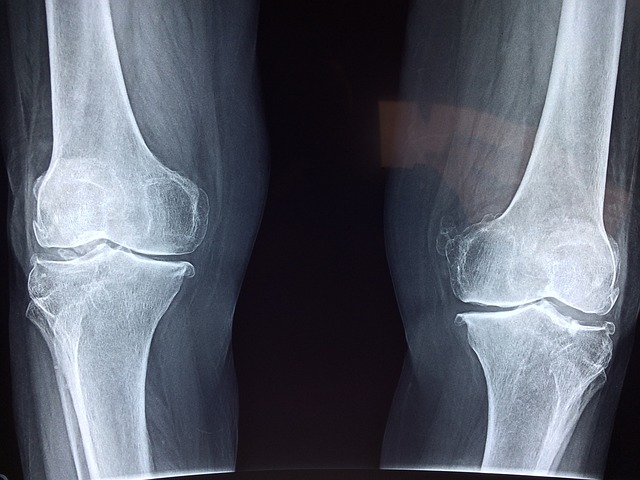

노화가 진행 되면서 자연스럽게 뼈가 약해지는 것을 느껴진다면 뼈건강에 주의를 해야 합니다. 골다공증으로 인해서 생기는 뼈 건강 문제는 뼈에 구멍이 나거나 약해져서 잘 부러지는 증상이 있기 때문에 뼈 건강에 각별한 주의가 필요하지만 노화로 인해서 자연스럽게 생긴다고 하여 방치하는 경우가 많이 있습니다. 뼈 건강은 젊었을 때부터 지켜야만 나이가 들어서도 튼튼한 뼈로 일상생활을 유지할 수 있습니다. 오늘은 뼈 건강에 도움을 주는 MBP 효능과 부작용, MBP 먹는 법에 대하여 알아보고 일상생활에서 뼈 건강에 도움을 주는 꿀팁에 대하여 알아보도록 하겠습니다.

평소에 뼈가 약하거나 노화로 인해서 뼈 골밀도나 골다골증이 걱정된다면 뼈 건강에 도움을 주는 MBP를 먹어주는 것도 도움이 될 수 있습니다. MBP 효능으로 잘 알려져 있는 효능은 뼈세포균형 유지, 뼈 형성세포 활성이기 때문입니다.

뼈에 좋은 것으로 잘 알려진 MBP 효능은 골다골증이 증상에 도움을 줄 수 있으며 골밀도를 높여서 뼈를 튼튼하게 만들어 줍니다.

평상시에 꾸준히 MBP를 복용해 주면 뼈 손상예방에 도움을 줄 수 있고 특히 노화가 진행되는 분들이라면 MBP 효능을 생각하여 꾸준히 복용을 해주면 뼈가 약해지는 증상 개선에 도움을 줄 수 있으니 꾸준하게 복용을 하여 뼈 건강에 도움을 주시기를 바랍니다.